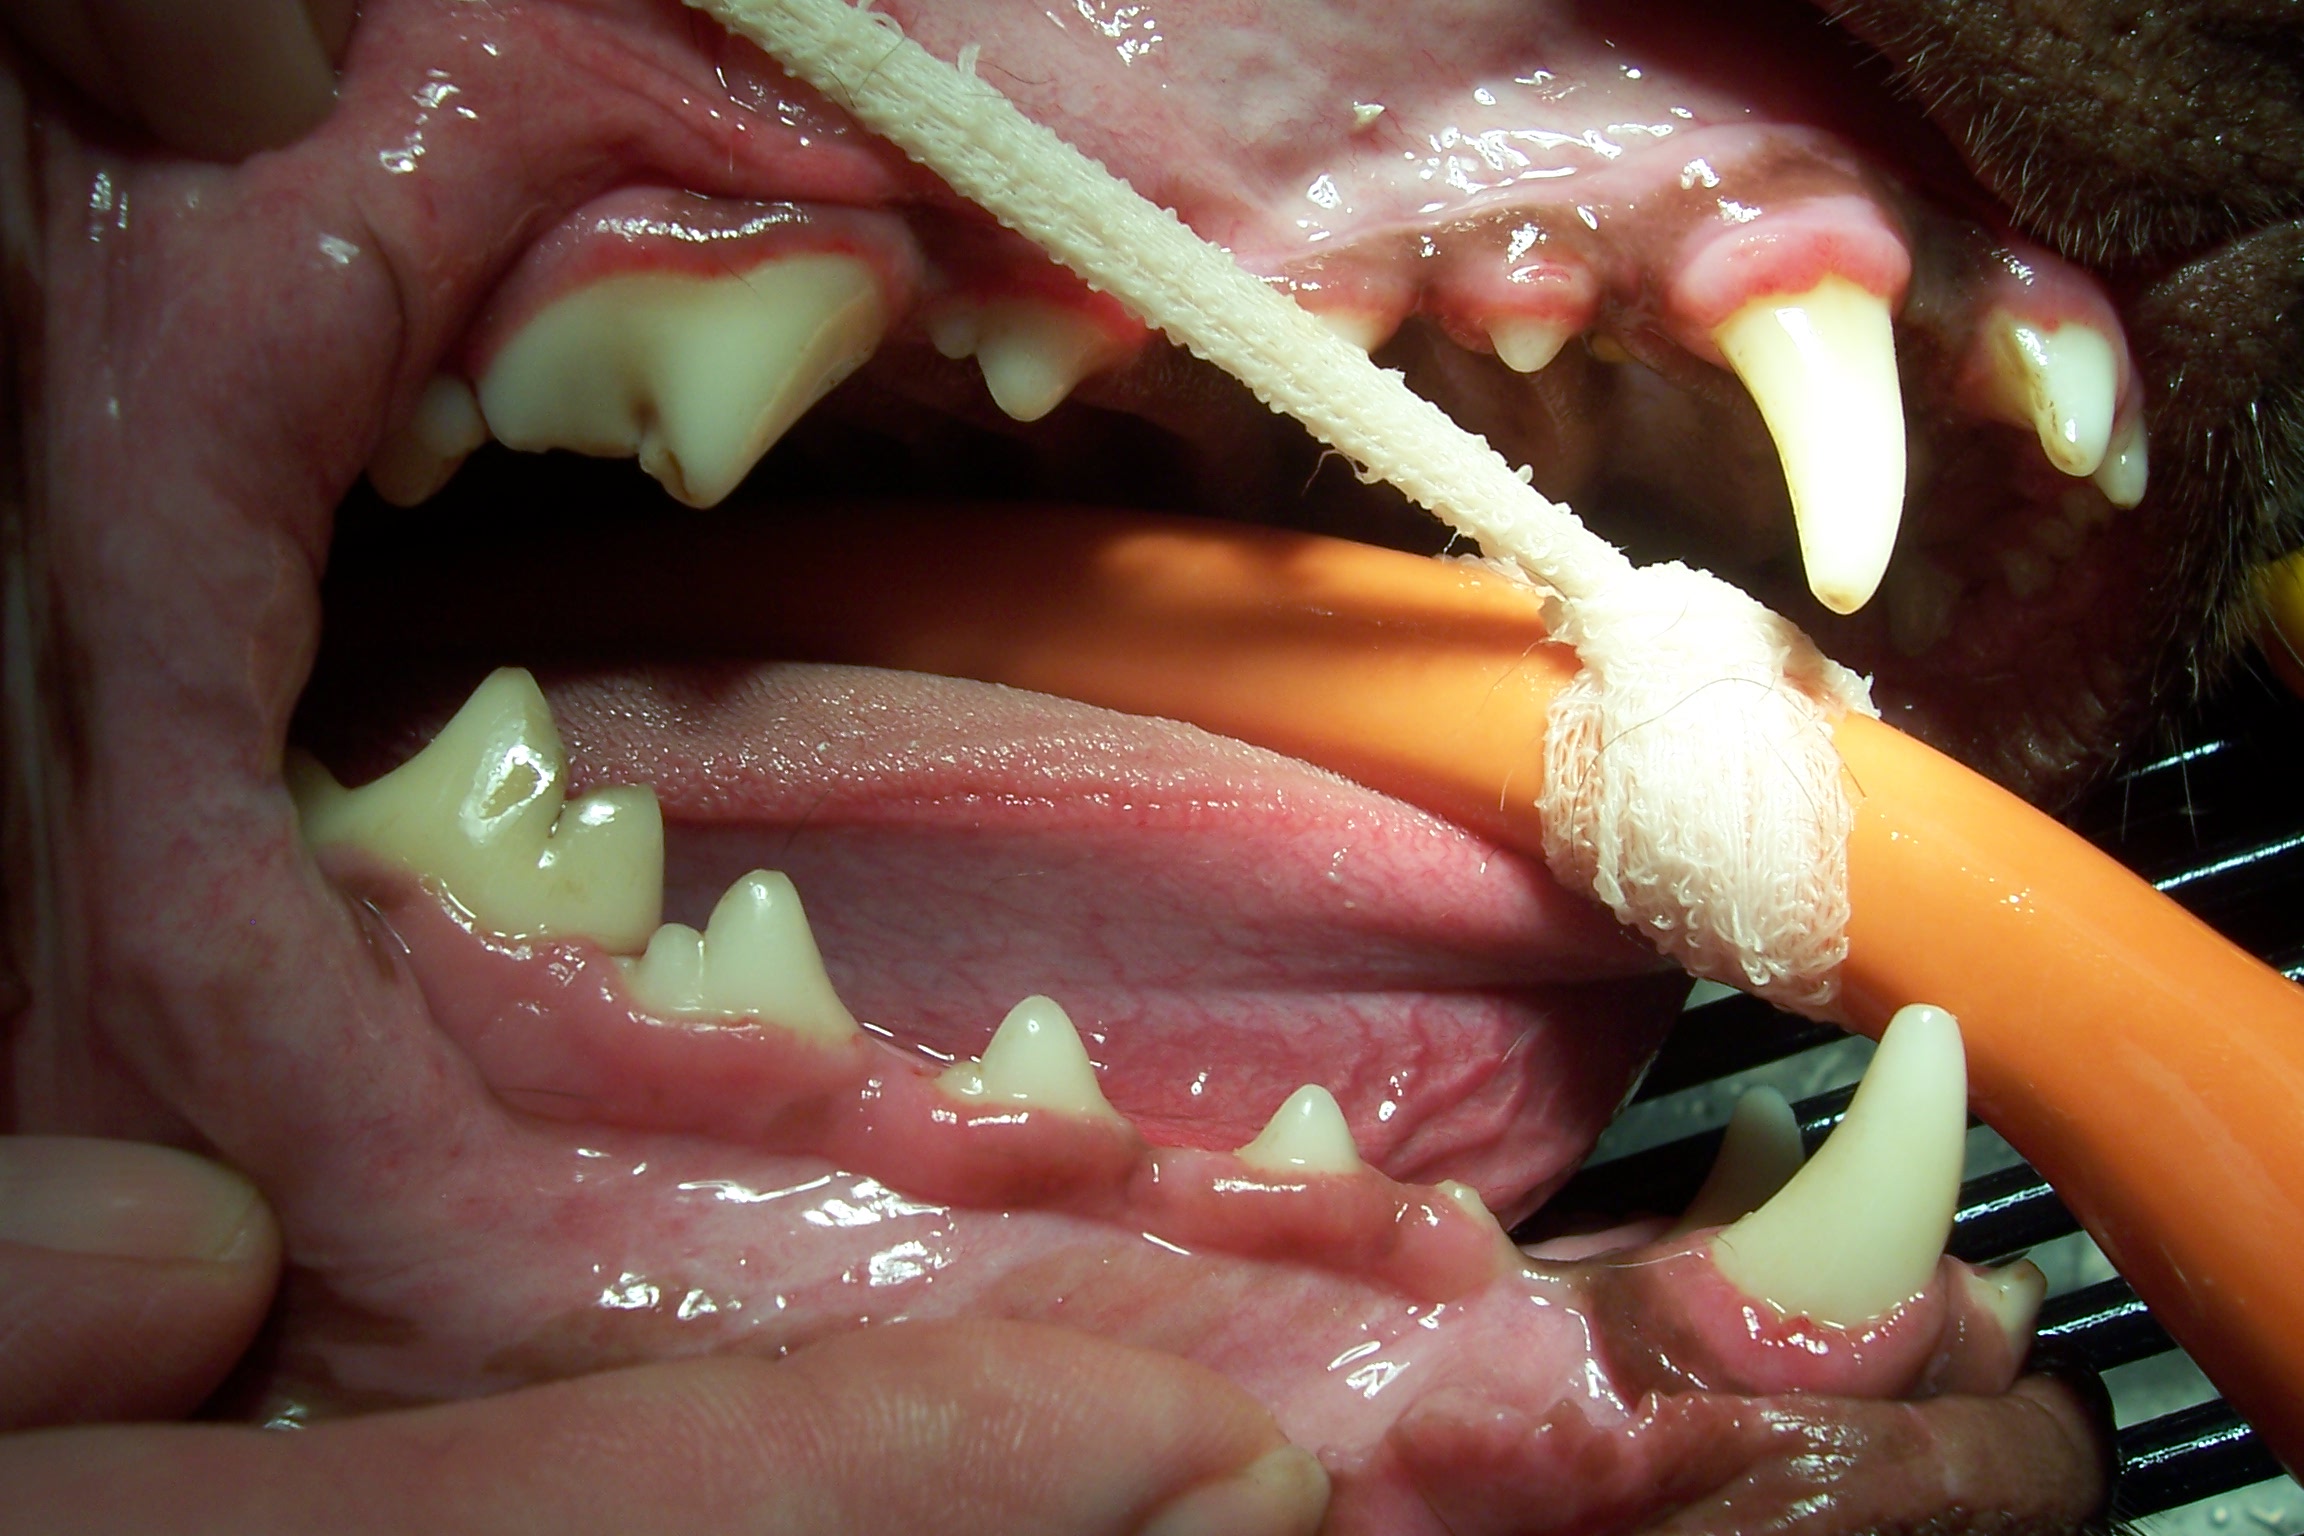

Mouth before dental cleaning

Healthier mouth after dental cleaning